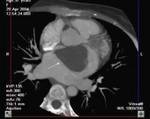

Methods: Twenty-two patients referred to our department with a suspected cardiac mass, previously detected by cardiac ultrasound, were evaluated by CT (12 patients) and MRI (4 patients). Six patients were examined by both modalities. In 2 cases of staging of a known primary neoplasm and one case of a suspected epicardiac lesion, positron emission tomography (PET-CT) was performed. The CT cardiac examinations were performed using a 16-slice multislice scanner with ECG gating. The MRI examination was performed on a 1.5 Tesla MRI scanner using an ECG-gated cardiac protocol and the PET-CT examination was performed on an integrated PET-CT four-slice scanner, using 370 mMBq of fluorodeoxyglucose.

Results: Twenty-two cardiac masses were successfully detected and their characteristics adequately delineated, including eight myxomas, one angiosarcoma, one ventricular lymphoma, one endocardiac metastasis, one epicardiac paraganglioma, and 10 cases of intracardiac thrombi.

Conclusion: CT and MRI are noninvasive imaging modalities which can delineate cardiac tumors and masses and provide essential information for adequate diagnosis, staging and treatment planning. Compared to cardiac ultrasound, CT and MRI are superior in preoperative planning.